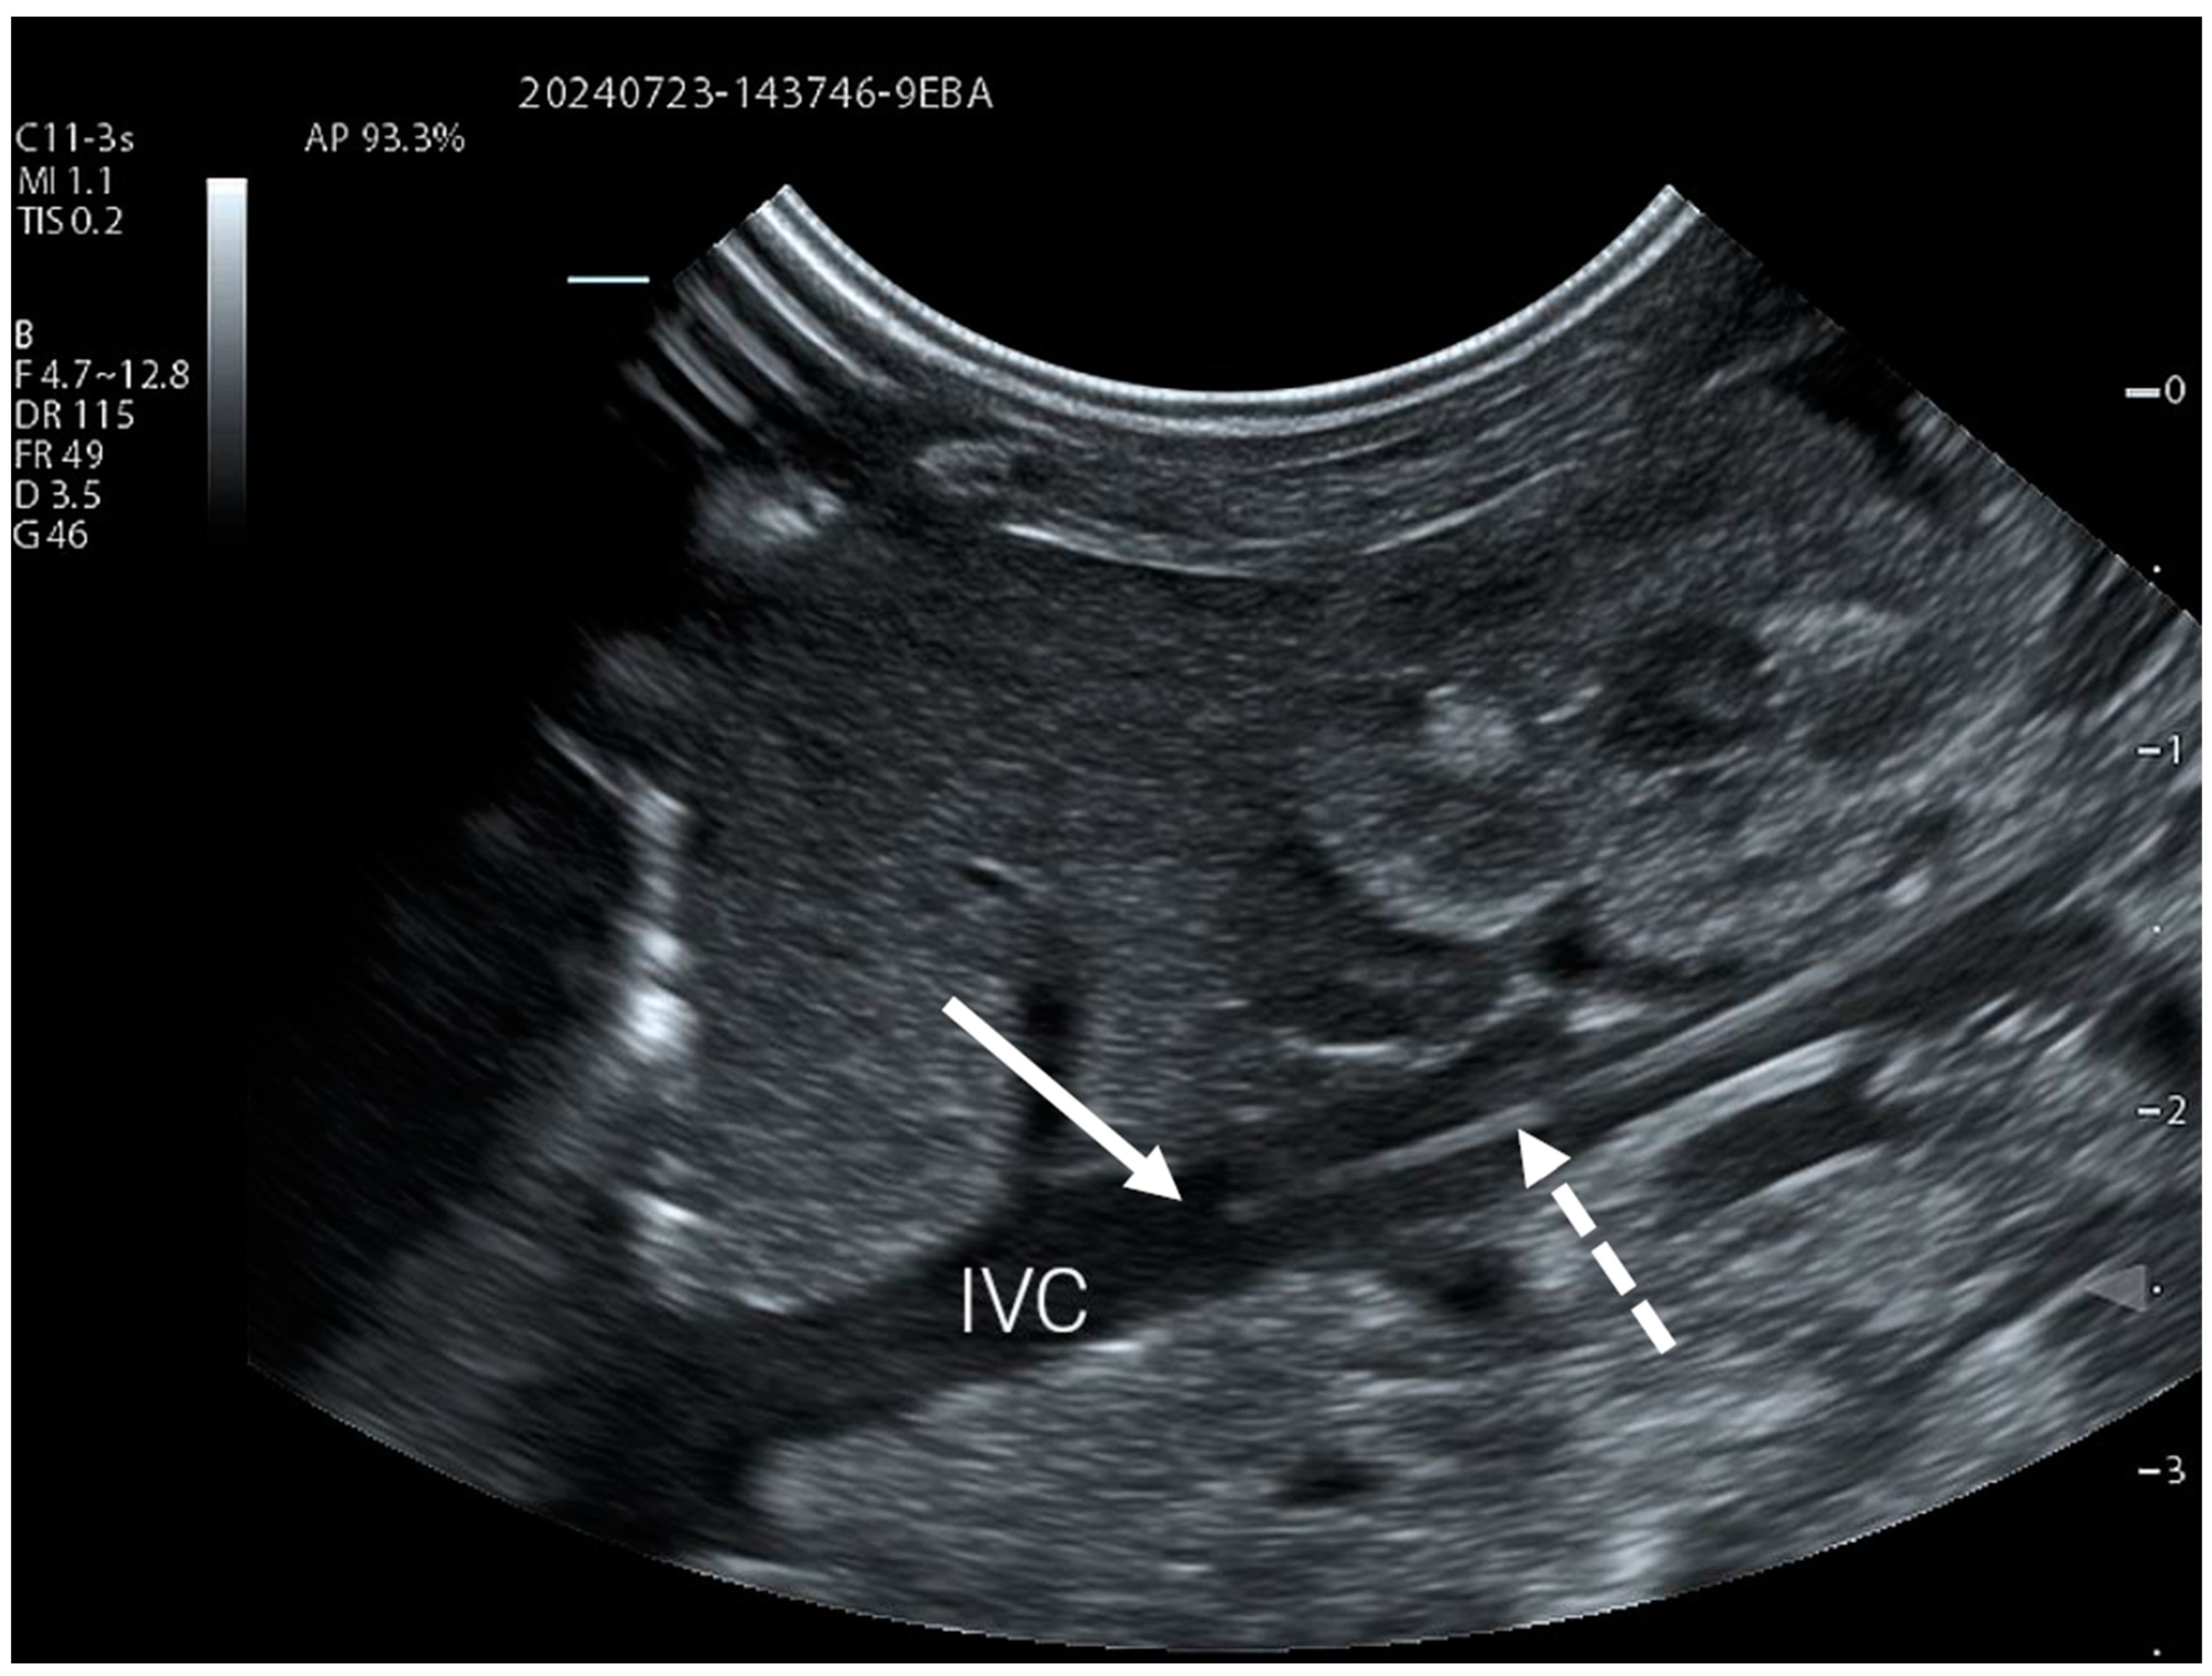

For PICC lines inserted from the lower limb, a lateral abdominal view of the right flank is used to visualise the IVC using either a curvilinear or linear transducer. This acoustic window is not only easy to use, but also allows visualisation of tributary veins to the IVC, such as the renal veins (Figure 1, Video S1). The right abdominal flank is more suitable for such a view, not only because of the anatomy of the vena cava, but also to avoid the artefacts caused by gastric contents on the left side.

Figure 1.

PICC catheter clearly visible in the inferior vena cava (IVC) using a simple lateral abdominal view. The catheter is marked with a dotted arrow, and the full arrow indicates its tip.